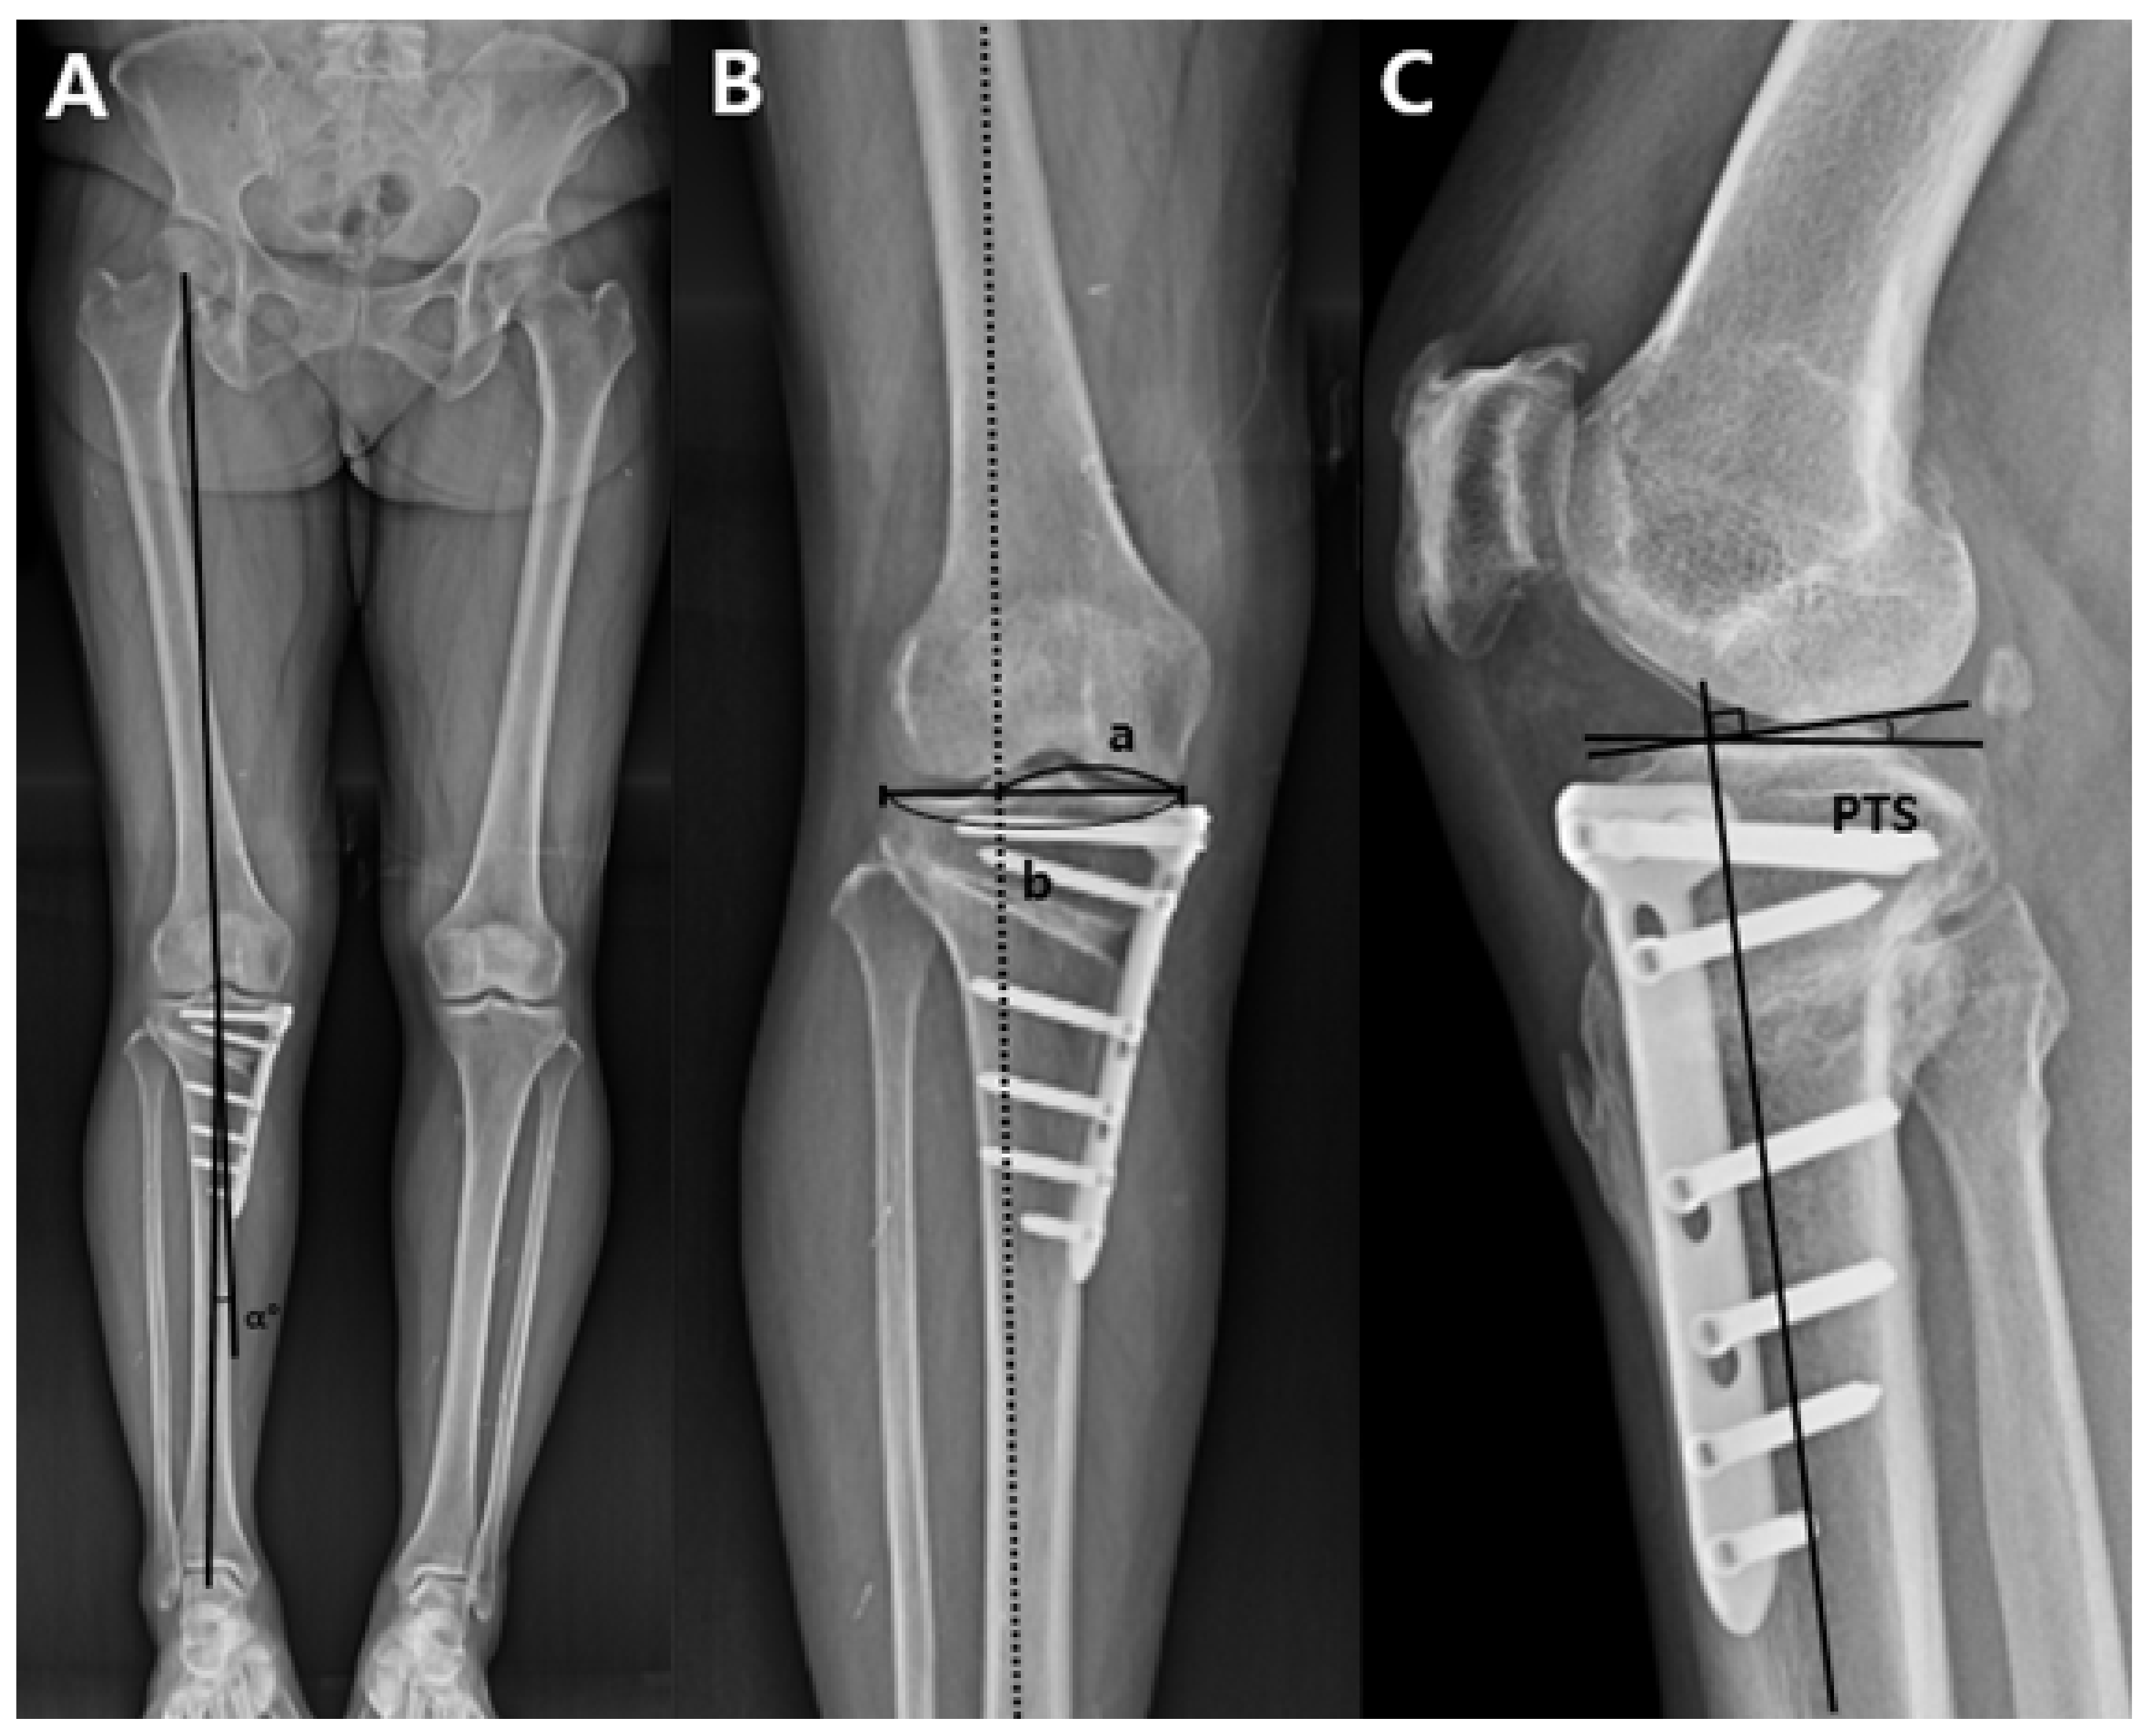

2.5. Measurement on Plain Radiographs

Figure 4. Measurement of the hip-knee-ankle angle, weight-bearing line ratio, and posterior tibial slope on the plain radiographs. (A) The hip-knee-ankle angle (α°) is formed by the first line drawn from the center of the femoral center to center of the tibial spine and the second line drawn from the center of the tibial spine of knee joint to the center of the superior articular surface of the talus in the ankle joint. The angle made by the intersection of these two lines was defined as the hip-knee-ankle angle. (B) The weight-bearing line was drawn from the center of the femoral head to the middle point of the superior articular surface of the talus on the full-length lower extremity standing radiograph. A tibial plateau line from the medial edge to the lateral edge of the proximal tibia on the joint surface was drawn thereafter. Weight-bearing line ratio (a/b) was calculated as the ratio of the distance from the medial edge of the proximal tibial plateau to the intersection of the weight-bearing line and the proximal tibial plateau line (a) to the entire length of the proximal tibial plateau line (b). The medial tibial edge was 0%, and the lateral tibial edge was 100%. (C) The posterior tibial slope is formed by the perpendicular line to the tibial shaft axis and the medial tibial plateau line on the true lateral view. posterior tibial slope = posterior tibial slope.